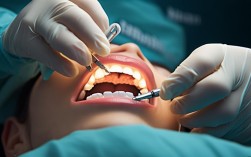

指在种植手术中使用激光技术进行软组织处理、消毒或骨切割。

- 精准微创:激光切割软组织更精准,出血少,肿胀轻。

- 消毒杀菌:激光可杀灭细菌,降低感染风险。